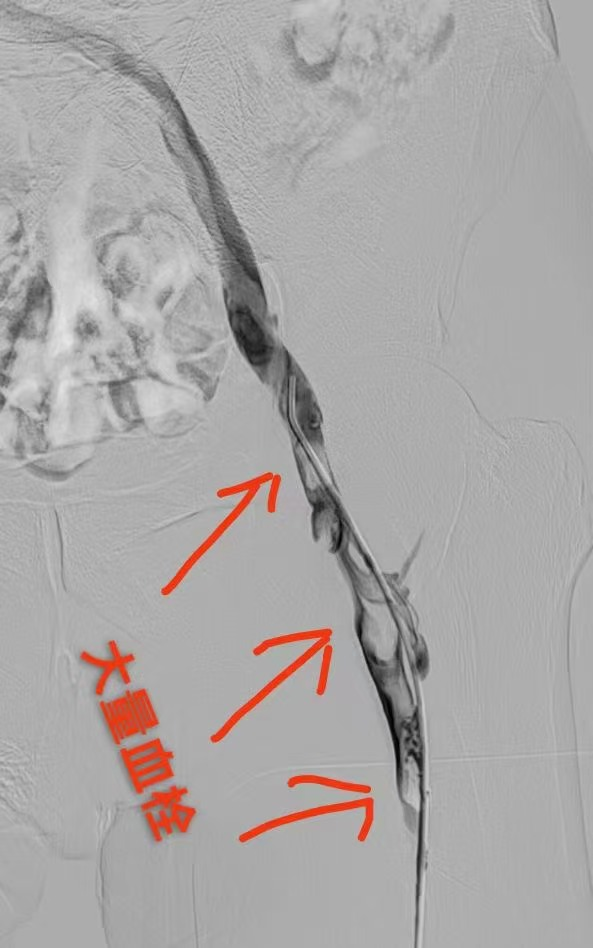

圖一為下肢血栓形成影像圖片 圖二為與圖一同部位經(jīng)過治療后血栓消失照片(圖片來源網(wǎng)絡(luò),如有侵權(quán)聯(lián)系刪除)

接下來就讓我們一起探索神奇的血栓消失過程,了解血栓的歸處旅程吧!血栓一般分為動脈血栓和靜脈血栓,動脈血栓進(jìn)展較快,后果也相對嚴(yán)重,會引起急性癥狀,并會短時(shí)間內(nèi)危機(jī)生命或?qū)е聡?yán)重身體損傷等,大部分動脈血栓的患者都需手術(shù)治療方式予以及時(shí)緊急干預(yù),如腦血栓、冠脈血栓、腸系膜動脈血栓、下肢動脈血栓等。相對于動脈血栓,靜脈血栓的患者的危急情況會稍好一些,無需緊急手術(shù)治療,可采用多種干預(yù)措施,當(dāng)然根據(jù)病情進(jìn)展情況,手術(shù)治療也是重要的備選方案,通常情況是使用注射或者口服抗凝藥物治療,如腸系膜靜脈血栓、下肢深靜脈血栓、上肢靜脈、門靜脈、卵巢靜脈等情況。??